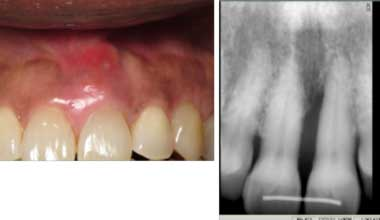

A 12-year-old African American female presented for treatment of localized rapidly progressive periodontitis on No. 19 and No. 30 prior to orthodontic treatment. Prior dental care included prophys and sealants. The LANAP protocol was performed at one appointment with local anesthetic.

Miss Novice before the LANAP protocol.

Miss Novice showed radiographic evidence of bone regeneration seven months post LANAP. She completed orthodontics and shows stable bone three years post LANAP.

Miss Novice after the LANAP protocol.